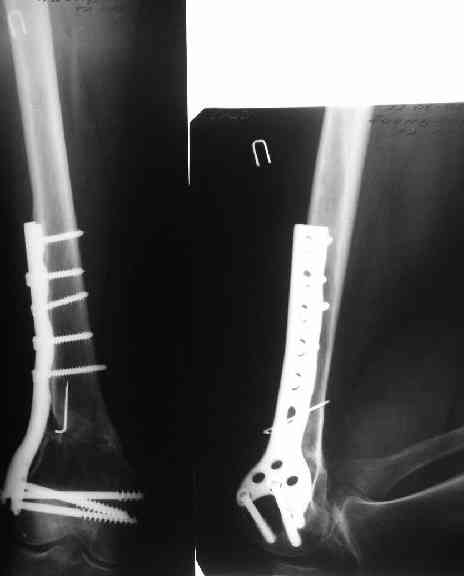

Пациенту М., 30-ти лет, 1,5 года назад в одной из московских больниц был выполнен остеосинтез бедренной кости штифтом UFN (диаметр штифта 9 мм).

К нам больной поступил с признаками ложного сустава бедренной кости, перелома

штифта и дистального блокирующего винта (images 1,2,3).

27 марта выполнено удаление блокирующих винтов (сломанный винт пришлось высверливать цапфен-бором), сломанного штифта (дистальный фрагмент удален через канал, образованный разверткой из коленного сустава - image 4),

рассверливание костно-мозгового канала, реостеосинтез штифтом UFN (при проведении штифта в дистальном отломке мы использовали поляризующий винт, диаметр штифта 10 мм). После операции в связи гемартрозом дважды (на 1 и 3 сутки) выполняли пункцию коленного сустава. Сейчас признаков скопления жидкости в полости сустава нет. Послеоперационные рентгенограммы - images 5, 6, 7.